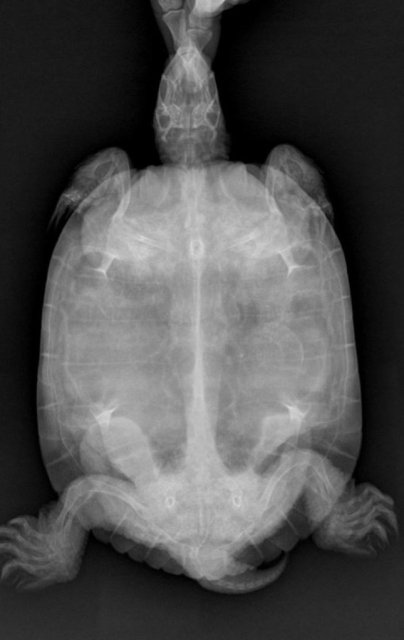

Елена_F Ваше имя: Цып Локация: Россия. г.Курск Опубликовано: 20 марта 2025 Автор Опубликовано: 20 марта 2025 @moth А по рентгену можно что- то сказать? Вроде газов меньше стало.

Консультанты moth Ваше имя: Мария Локация: Москва Опубликовано: 20 марта 2025 Консультанты Опубликовано: 20 марта 2025 @Елена_F врач расшифровку рентгена ещё не делала? по мне лучше стало, но надо чтобы врач смотрела и расшифровала, потому что здесь ошибка будет очень дорого стоить

Елена_F Ваше имя: Цып Локация: Россия. г.Курск Опубликовано: 20 марта 2025 Автор Опубликовано: 20 марта 2025 @moth Расшифровку она не делала, но для сравнения я ей показала старый снимок и она мне показала, что на новом снимке меньше затемнений, т.е. газы уходят. С сердцем тоже вроде всё нормально, осмотрела язык.